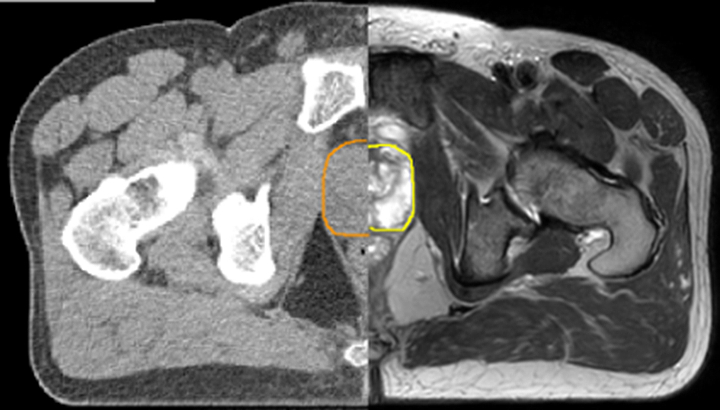

With its exceptional soft-tissue visualization capabilities and wide range of image contrasts, MRI has become a powerful tool to help more precisely define tumor boundaries. This is particularly important as it has been established that there is a high degree of uncertainty in target volume delineation, and it is even reported to represent the largest uncertainty in the entire radiotherapy process for most tumor sites**. Better visualization of the target area and nearby organs-at-risk is a key factor in enhancing target volume delineation. MRI’s expanding role also can be attributed to its functional imaging capabilities, which can inform both target characterization and treatment response.

With its superior soft tissue contrast compared to CT, MRI offers exquisite visualization of tumor boundaries and proximity to nearby critical structures.

The ability to tune contrasts can provide even more valuable information about tumor characteristics and tumor extent to facilitate enhanced delineation, and also provides possibilities for dose boosting strategies. - Functional imaging